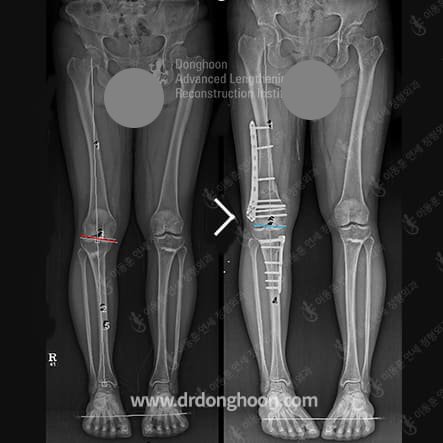

예시1.- 잘못된 절골 위치로 인한 관절선(jointline)의 기울기가 증가한 합병증을 재수술을 통해 교정함.

다리 변형(휜다리)의 정확한 위치를 분석하고, 변형이 있는 위치에서 교정수술을 해야 합니다.

겉으로는 같은 모양의 휜다리(오다리 또는 엑스다리 등)이더라도 실제 다리가 휘어진 위치는 각기 다를 수 있습니다. 오다리의 경우 종아리뼈(경골)에, 엑스다리의 경우 허벅지뼈(대퇴골)에 변형이 있는 경우가 많지만 항상 그런 것은 아니기 때문에 늘 정확한 분석이 필요합니다.

또 복합적인 변형이라도 정확하게 분석하고 치료가 가능한 의료진과 함께 하십시오. 실제 변형의 위치와 관계없이 수술하는 경우 겉으로는 좋아진 것처럼 보일지 모르나 실제로는 또 다른 변형을 만드는 결과를 초래할 수 있습니다.